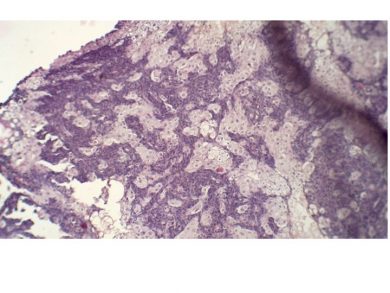

SEBACEOMA.005